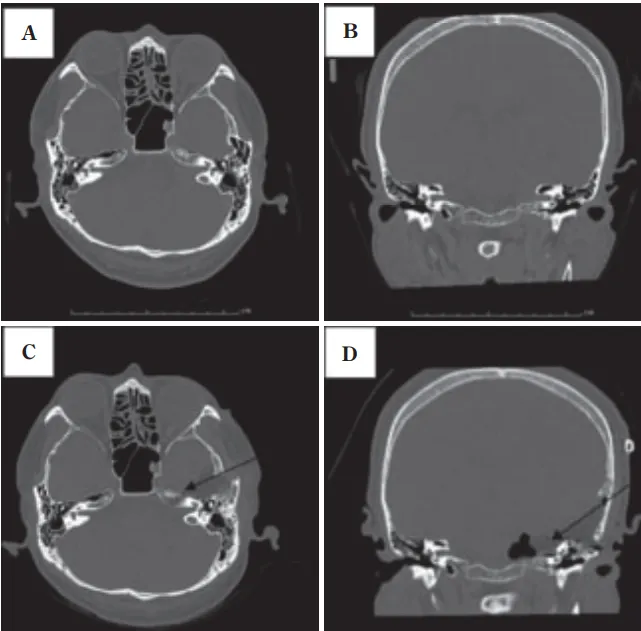

术后,患者出现了面神经麻痹症状,幸运的是,经过一年的恢复期,患者的面神经麻痹得到了明显缓解。复查影像显示,内耳道前壁和上壁的切除范围精准,颈静脉球得到了完好保护,肿瘤实现全切,无复发迹象。